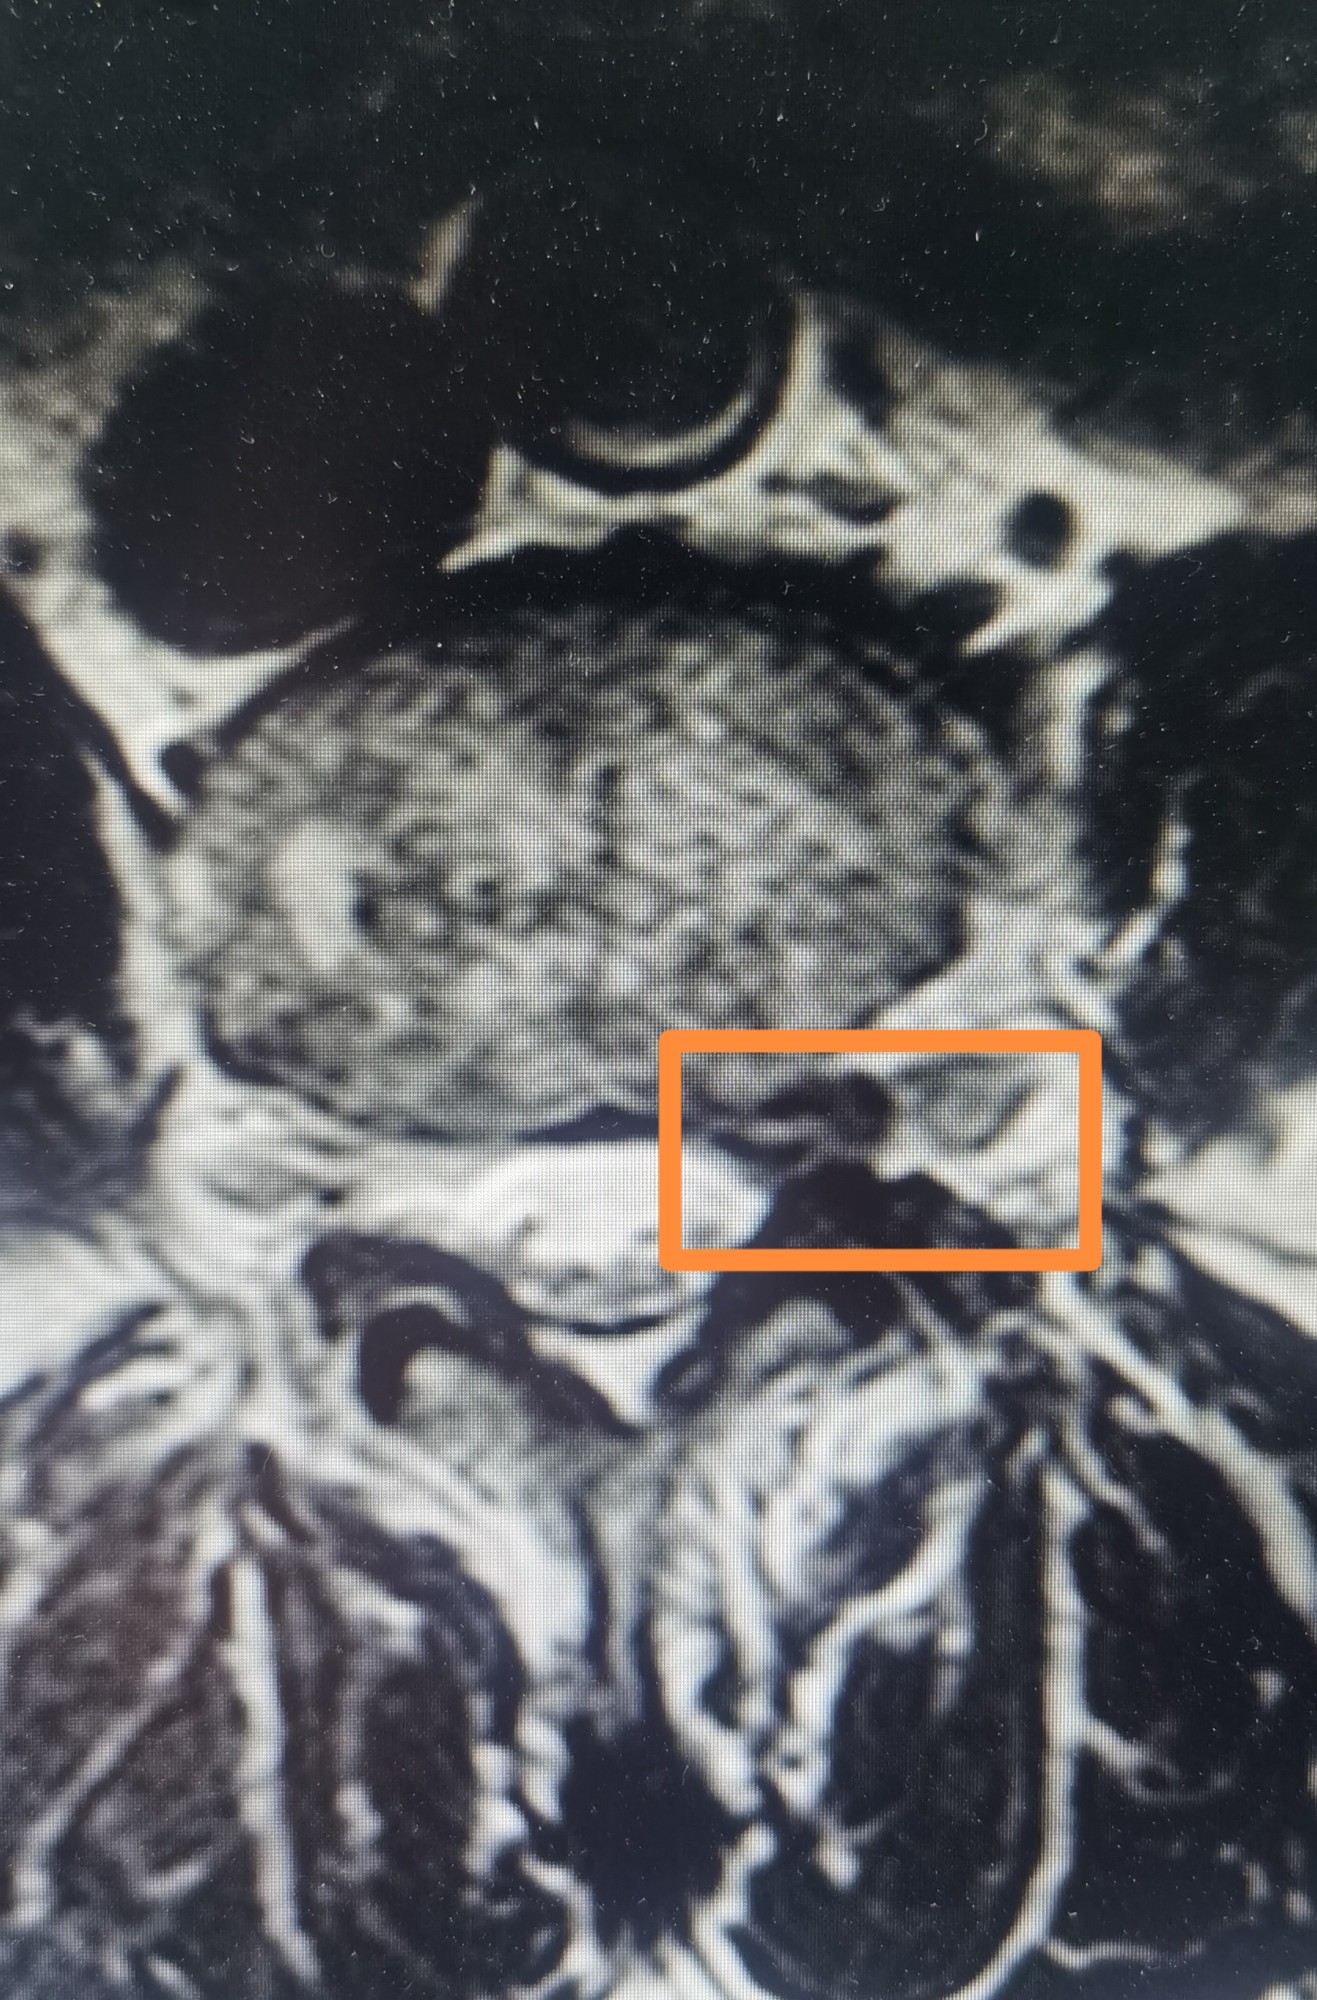

磁共振和CT椎间盘脱出1